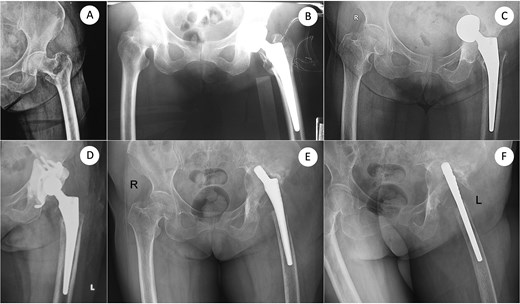

A 73-year-old woman presented with severe bone loss of the left proximal femur and extensive acetabular deficiency with pelvic discontinuity (Fig. 1). Initial treatment in 2017 for a displaced femoral neck fracture was bipolar hemiarthroplasty (Fig. 2A and B). After a new injury in 2019, an acetabular fracture with intrapelvic migration of the bipolar head occurred (Fig. 2C), leading to conversion to total hip arthroplasty with a revision acetabular component supported by a cup–cage (“trap”) construct (Fig. 2D). In 2023, PJI developed with loosening of both components; the acetabular component was explanted and a central pedicled vastus lateralis flap transposed to manage dead space (Fig. 2E and F). In May 2024, the femoral component was removed (Fig. 3A). CT confirmed mixed cavitary–segmental acetabular defects and marked metaphyseal loss of the proximal femur (Fig. 3B). After normalization of inflammatory markers and soft-tissue healing, salvage re-revision THA was performed. Acetabular reconstruction used a 52-mm porous shell–cage; two 45-mm tongues engaged host ilium and ischium, and cavitary defects were filled with antibiotic-loaded polymethylmethacrylate. Fixation comprised three intra-shell screws, four rim screws, and two tongue screws (Fig. 3C). On the femoral side, 2 cm of compromised proximal femur was resected to bleeding bone; the canal was reamed to 15 mm for circumferential endosteal contact. A modular tapered, fluted stem (14 × 260 mm) achieved distal fixation, supplemented by two distal interlocking screws; prophylactic cerclage mitigated iatrogenic fracture risk (Fig. 3C). Postoperatively, weight bearing advanced as tolerated. Serial AP pelvis radiographs showed a stable cup–cage without migration or progressive radiolucency and a well-seated stem without subsidence. At 10 months there were no complications, no infection or dislocation, and the patient ambulated with a cane; radiographs remained stable (Fig. 2D).

Definitive salvage re-revision THA: Defect assessment after femoral explant (AP and 3D-CT) and final reconstruction. (A) AP pelvis after removal of the femoral component showing severe acetabular and proximal femoral bone defects. (B) Three-dimensional computed-tomography (3D-CT) reconstruction corresponding to (A), confirming mixed cavitary–segmental acetabular defects. (C) Immediate postoperative AP radiograph after salvage re-revision total hip arthroplasty using a cup–cage acetabular reconstruction and a 260-mm modular tapered femoral stem secured with two distal interlocking screws. (D) AP X-ray taken 10 months after re-revision. AP, anteroposterior; 3D-CT, three-dimensional computed tomography; THA, total hip arthroplasty.